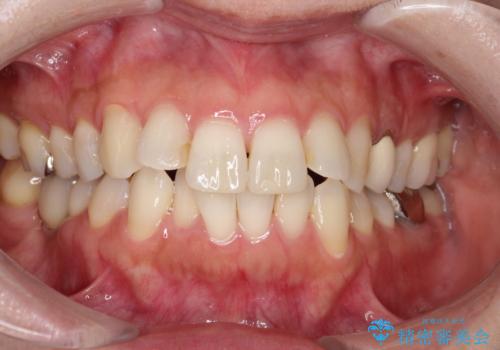

前歯のデコボコをインビザラインでスッキリと仕上げる

マウスピース矯正で前歯のガタつきを改善

上下前歯のデコボコをきれいに インビザラインによる矯正治療